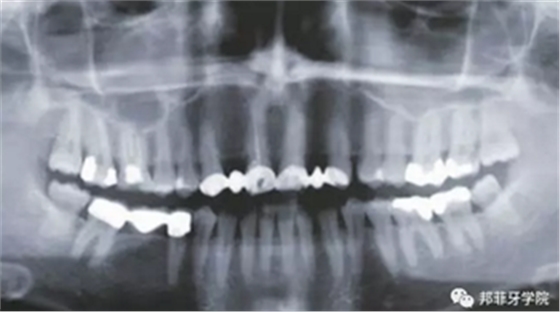

26歲女性患者,雙側上頜側切牙先天缺失,對原有修復體的“形態(tài)”、“光澤”等方面不滿意,希望重新修復(圖1&2)。12及22原為粘接橋修復,11根管治療史;拆除原修復體后余鄰牙完整,未見病理性探診深度。無系統(tǒng)疾病史?;颊咂谕递^高,告知治療流程佩戴臨時卡環(huán)義齒等(圖3)、費用、風險后表示接受治療。

圖2:治療前全景片